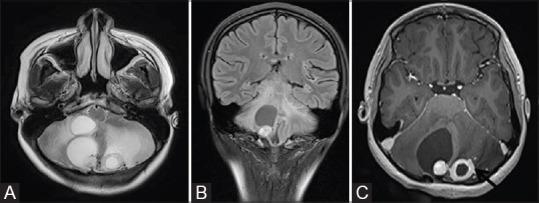

Phakomatoses or Neurocutaneous syndromes are a heterogeneous group of disorders and have variable inheritance pattern. Currently, more than 30 entities are included in this group. These disorders primarily affect the central nervous system; however, skin, viscera, and other connective tissues can also be involved with variable clinical presentation. We will describe and illustrate the various radiological findings of the common entities through the iconography of the cases presented to our department.

phakomatoses或神经皮肤综合征是一组异质性疾病,具有可变的遗传模式。目前,该组包括30多种疾病。这些疾病主要影响中枢神经系统;然而,皮肤、内脏和其他结缔组织也可能受累,临床表现各异。我们将通过提交至我科病例的影像学表现来描述和说明常见疾病的各种放射学表现。